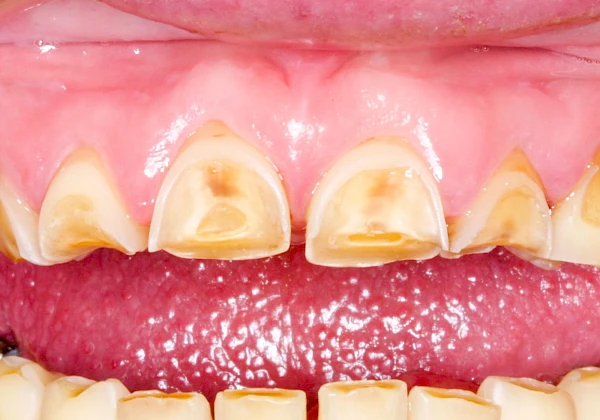

Auswaschung (Erosion) dagegen ist eine Verschleißerscheinung der Zähne aufgrund von immer wiederkehrenden Säureangriffen durch die Nahrung, verstärkt zum Beispiel durch den Genuss säurehaltiger Getränke oder Speisen. Auch bei Menschen mit einer Essstörung (z. B. Bulimie) können die Zähne durch die Magensäure ausgewaschen erscheinen.